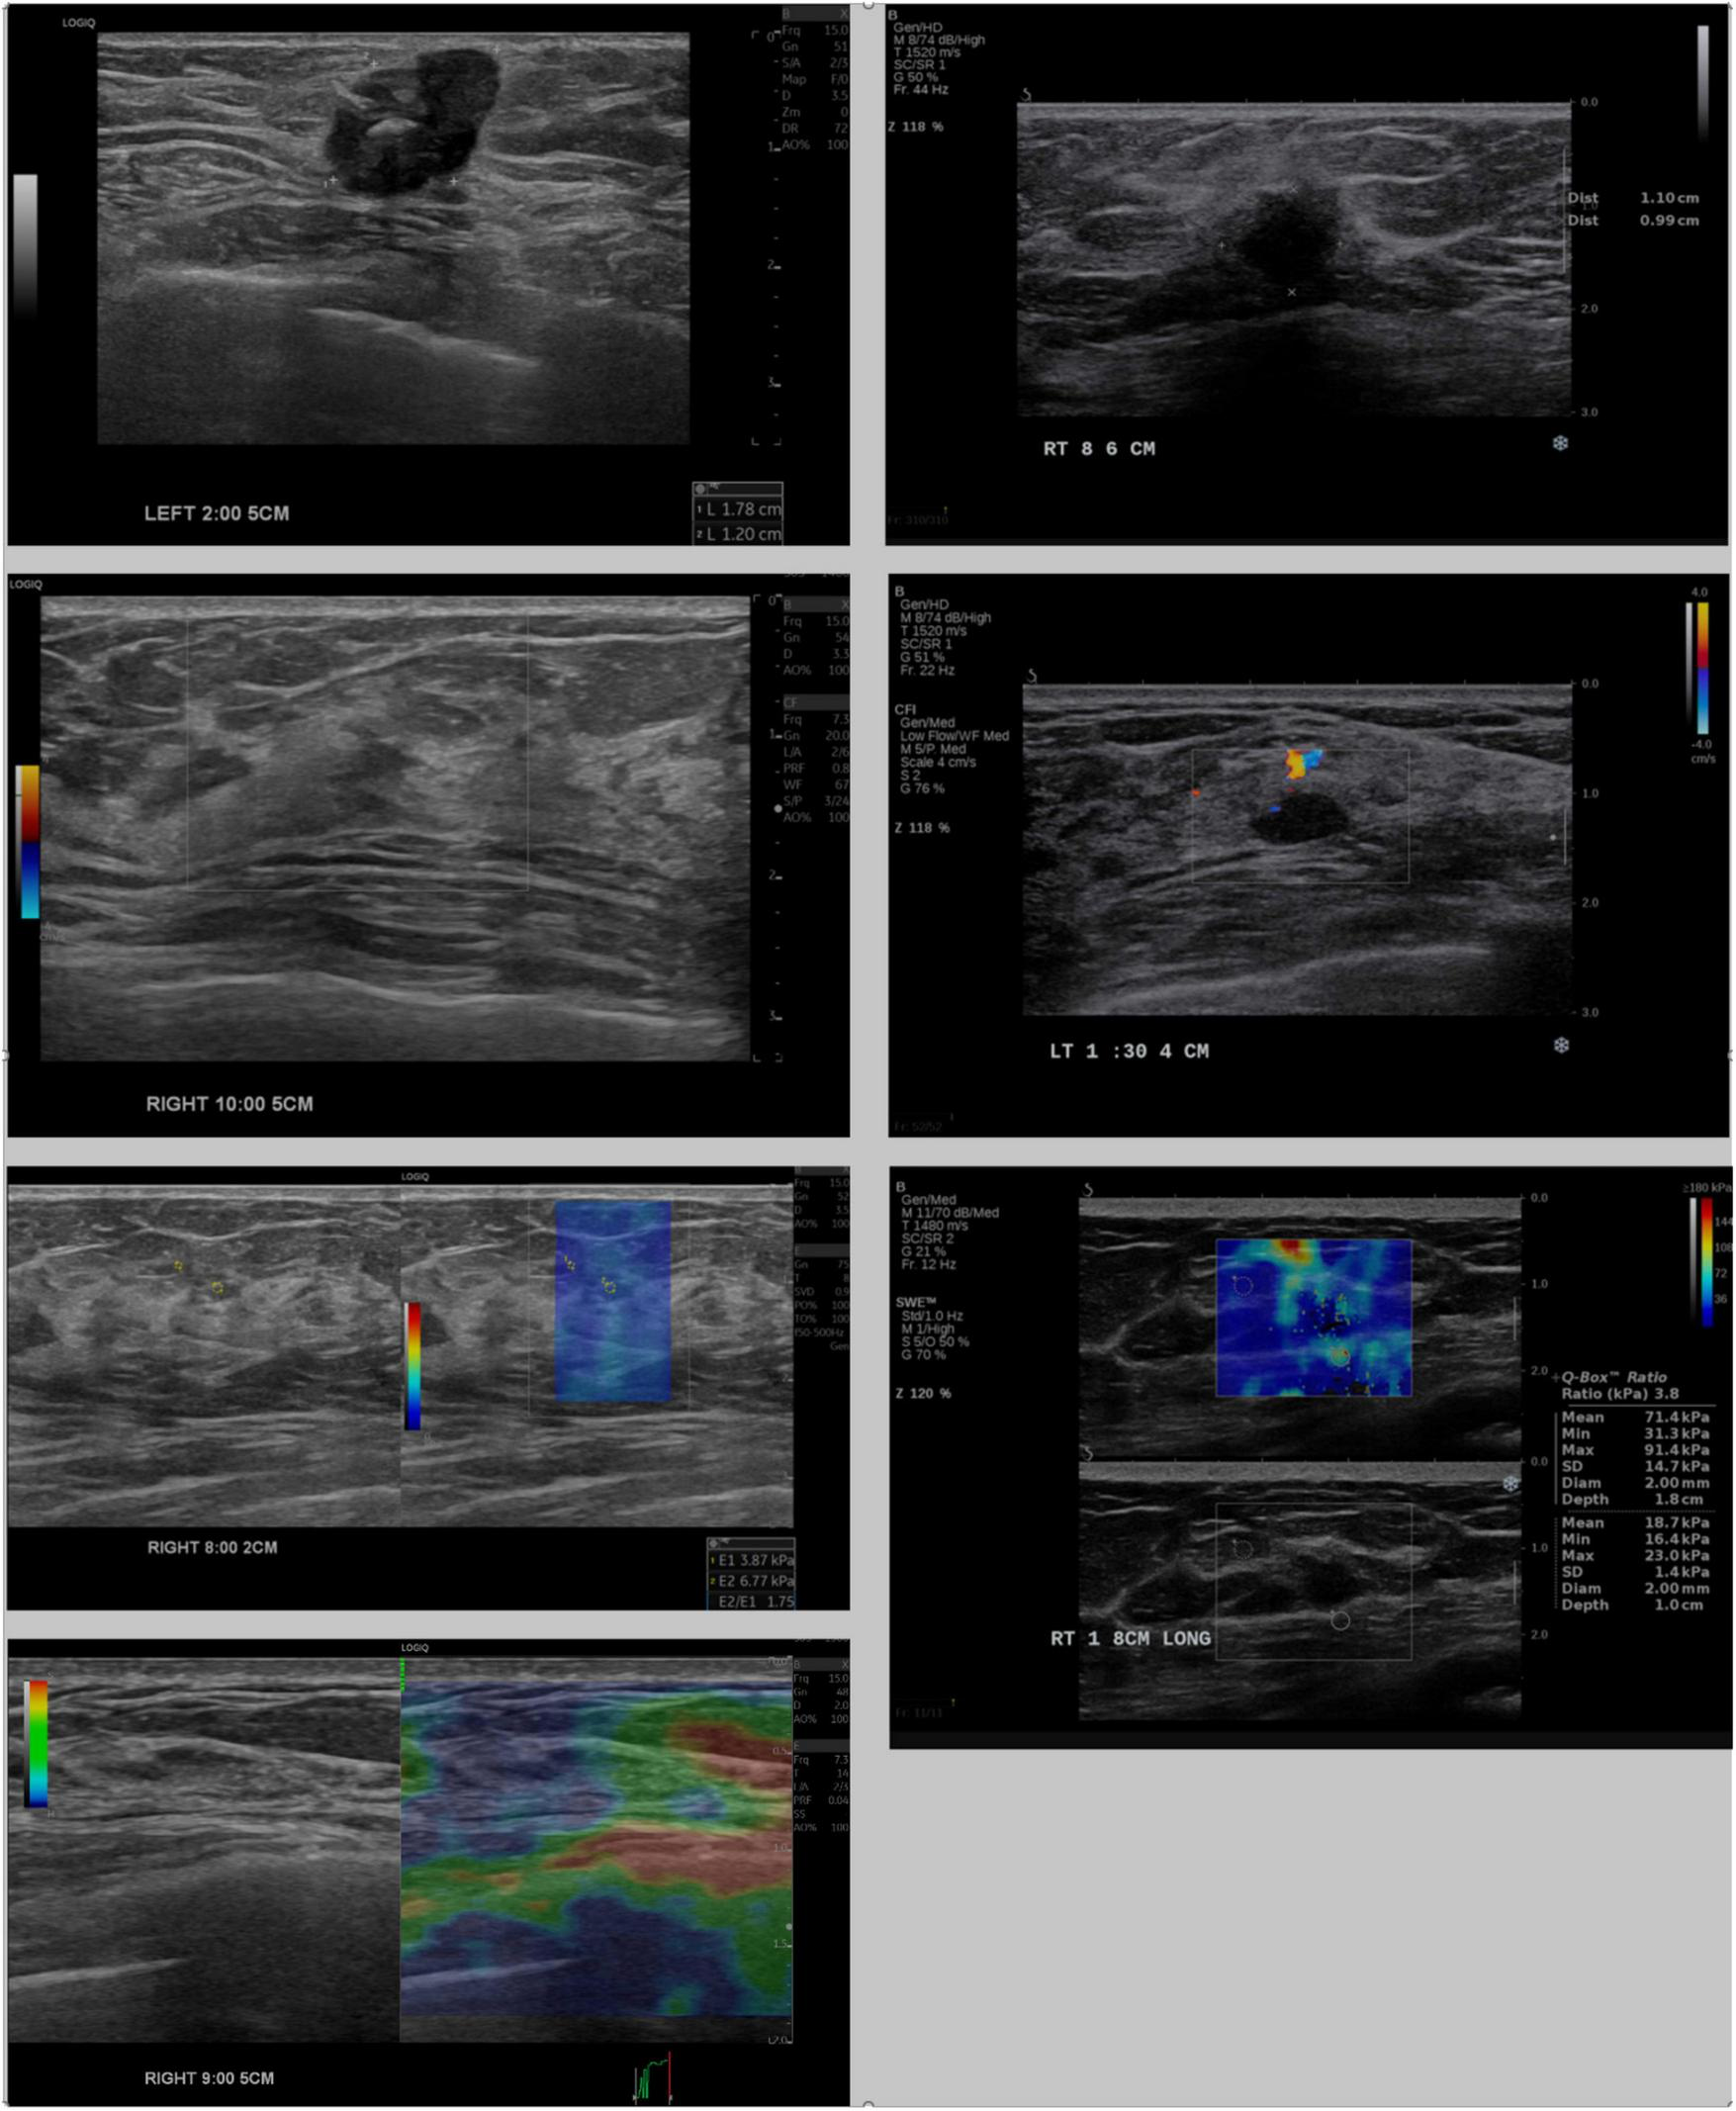

The IC-LLM module classifies breast US scans into four imaging types: B-mode, shear-wave elastography, strain elastography, and Doppler elastography, each characterized by distinct visual attributes. For instance, B-mode images lack color legends, whereas shear-wave elastography images include the text “kPa.” Doppler images feature irregular contours with units, such as cm/s, whereas strain elastography images display colored bars with units, such as s/h. Figure 2 illustrates these visual distinctions, highlighting variations in annotation placement, location, and depth information across different US machines.

FIGURE 2

Comparison of breast ultrasound images acquired from LOGIQ E10 (left) and Aixplorer (right). Rows show, from top to bottom: B-mode images with annotated mass sizes, Doppler images, shear-wave elastography, and strain elastography (available only for LOGIQ E10).